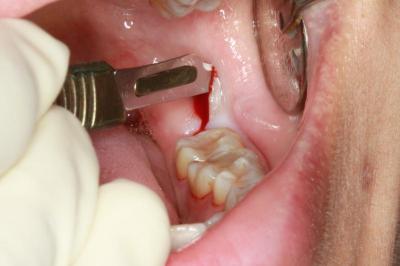

Сложное удаление может занять от 30 до 60 минут, требует применения сильных анестетиков, использования специального хирургического инструментария.

Экстракция проводится с рассечением десны и предполагает ее сшивание впоследствии. Ввиду сложности операция должна проводиться только квалифицированным хирургом-стоматологом.

- Надрез десны, отслоение её от кости, осуществляется, чтобы добраться до удаляемого зуба и его корней.

- Установка дренажа для очищения раны от гноя (при его наличии) с последующей обработкой лунки антисептиком.

- Зашивание рассечённой десны посредством наложения саморассасывающихся швов.